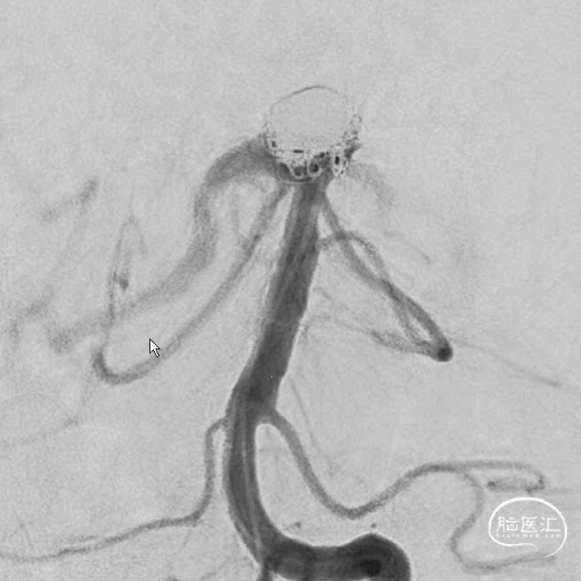

造影显示,左侧大脑后动脉起始似乎还是受到圈的小小影响,最终决定还是把支架放上。

支架释放完毕,感觉还是不太死心,于是调整了微导管几次,由于弹簧圈和支架的阻挡,还是调不进去,如果继续尝试,可能有增加支架内形成血栓的概率和导管可能戳破动脉瘤的风险。于是绝定再造个影看看。

这个角度,感觉残留一些。

换了个角度,感觉还可以。

标准侧位发现,这个位置有些残留,角度还是比较刁的,不太好到位。虽然有这么一点小遗憾。但是从患者是未破裂动脉瘤,及减少患者风险为第一位的角度上看,还是可以考虑一下。因此毅然决定收手。术后患者安好。